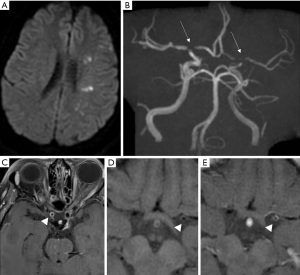

A multi-contrast vessel-wall MRI protocol with luminal imaging could help differentiate between moyamoya disease, atherosclerotic-moyamoya syndrome and vasculitic-moyamoya syndrome significantly better than luminal imaging alone (46). It has also been reported that Moyamoya disease may also have different presentations depending on the phase of the disease. The most common pattern to be identified has been concentric enhancement on bilateral distal internal carotid arteries and shrinkage of a middle cerebral artery, regardless of symptoms (47). The same group reported that eccentric enhancement corresponded with acutely infarcted territories, which is a link to vulnerable lesions in Moyamoya disease (Figure 4). There is also evidence of lower vessel wall cross-sectional area in patients with Moyamoya disease compared to vessels of patients with ICAD.